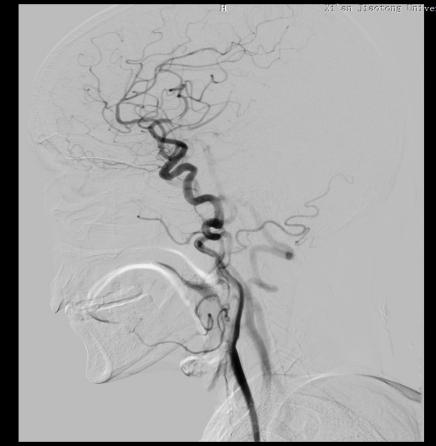

患者武某,女,75岁,因言语含糊伴右侧肢体无力3小时入院。行头颅CT未见明显出血病灶,颅脑DWI示:左侧额叶及枕叶可见新发病灶。遂以“急性脑血管病”收住神经内科。结合患者病史系统完善检查,既往有“心房纤颤”病史,未使用药物治疗,有“高血压”病史5年余,测最高血压180mmHg,现口服坎地沙坦降压,自诉血压控制尚可。有脑心血管造影检查手术指征,无手术禁忌症,建议患者进行全脑血管造影及冠脉造影术。而完成两个部位造影就意味着要行两次手术,两次手术不仅增加患者的痛苦,还给患者增加了经济负担。急患者之所急,想患者之所想,经过神经内科张茹副主任、范清雨医生和心血管内科蒋伟副主任医生详细讨论并做好全面评估后,共同为患者制定了冠脉造影检查后行全脑血管造影检查的手术方案,既可以明确病情,又可以减少患者痛苦。

告知患者及家属全脑血管造影及冠脉造影相关手术风险后,家属表示理解并签字同意全脑血管造影及冠脉造影术。手术如期进行,在神经内科导管室为患者实施了“经股动脉行全脑血管造影术+冠状动脉造影术”。手术历时1小时05分,科室之间配合默契,顺利完成此次手术。

此项技术是在脑血管造影基础上同时进行心血管造影,一次穿刺就可以检查“脑”血管和“心”血管,将原本需要两次才能完成的检查一次性完成,不仅减少了患者反复动脉穿刺的痛苦,也极大地缩短了检查时间,降低了检查及治疗费用。此次多学科联合诊疗,制定脑心血管同时造影,为患者寻找出了病因,共同为患者的生命健康保驾护航!